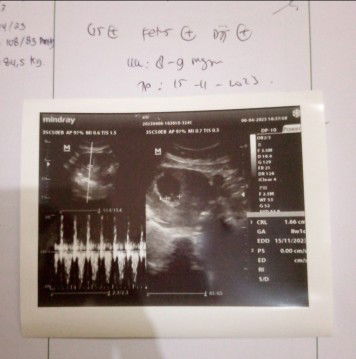

Ini hsil USG saya Bun kmrin sore..Kta y usia kandungan baru 8-9 Minggu sedangkan prediksi bidan udh 9-10 Minggu,😬yg lebih akurat yg mna Bun

akurat usg